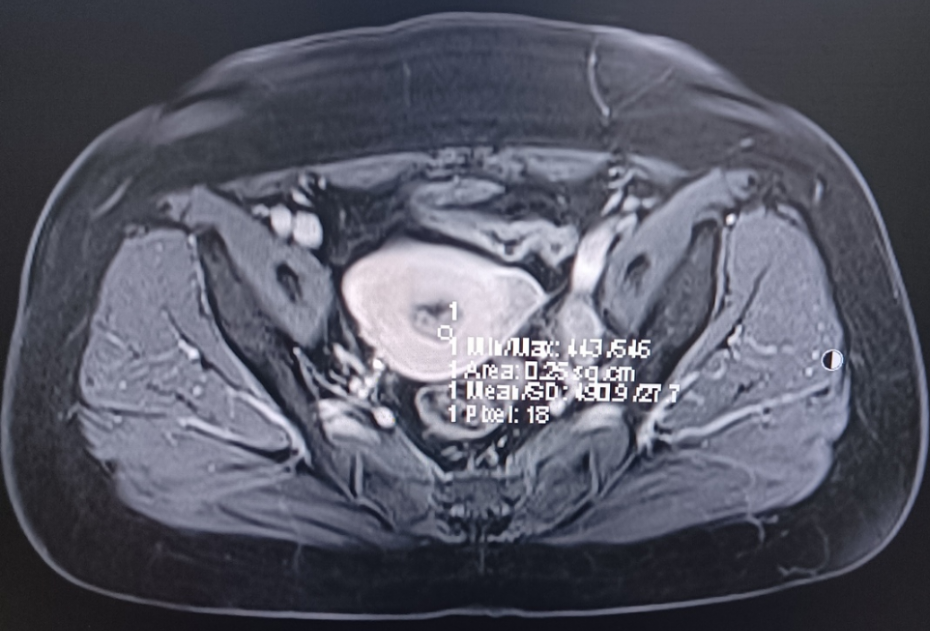

MRI: